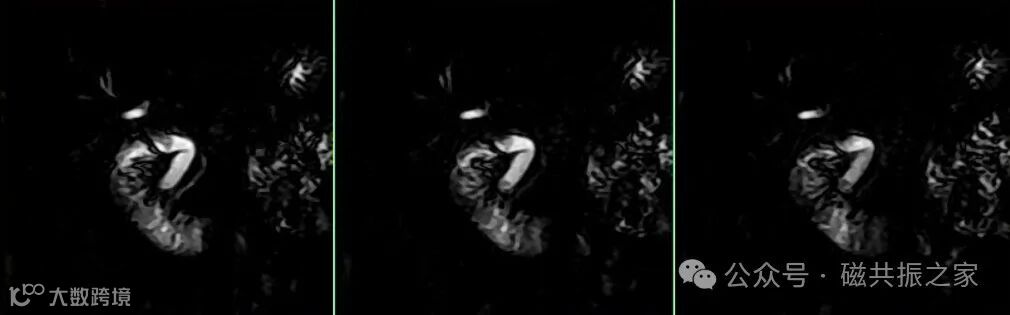

极速成像:单次屏气扫描即可完成整个胰胆管成像,大幅减少运动伪影风险,尤其适合配合度高的患者。 病变检出优势:可对蠕动、搏动等运动的“冻结”,该方式对胆囊结石、胰管狭窄等小病变的显示更清晰,对比更佳(边缘更为锐利),研究表明在高场强的加持下,对肝内胆管分支的解剖细节优于呼吸门控,如下图。